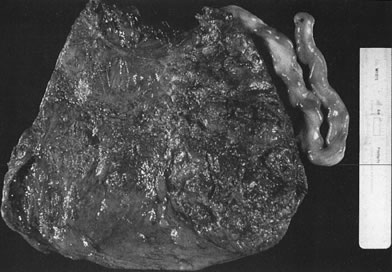

Early in gestation, the entire circumference of the placental sphere is covered by villi. As the gestational sac expands and the abembryonic chorion bulges into the uterine cavity, the blood supply to the villi becomes attenuated. The abembryonic villi atrophy, eventually forming the bald chorion. If villi other than those that will form part of the chorion frondosum can obtain a blood supply from, for example, the opposite uterine wall, they can continue to grow and arborize, developing into an accessory lobe. Predisposing conditions include uterine crowding (e.g., multiple gestations or septated uteri) or implantation in the lower uterine segment, which fails to expand as readily as the fundus. An accessory lobe is generally not associated with any maternal or fetal compromise except when an accessory lobe causes partial placenta previa or vasa previa (in which case fetal exsanguination may occur) or when an accessory lobe is left behind in the uterus after delivery (leading to maternal postpartum complications of retained secundines). A more extensive variant of this process is placenta membranacea (Fig. 9), in which there is more extensive or complete persistence of villi over the entire sphere of the chorion. This condition carries significant risks because it obligates a placenta previa and may be associated with significant acute or chronic maternal and/or fetal bleeding in the third trimester.

Fig 9. Failure of regression of the chorion laeve will result in placenta membranaceae. The placenta assumes the shape of the uterine cavity, is thin, and always has an abnormal umbilical cord insertion.